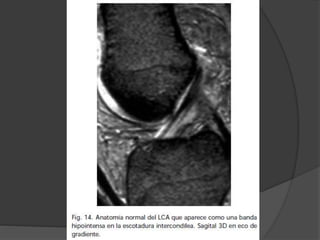

LCA

 Roturas crónicas

 no hay edema ni sinovitis

 pequeño derrame articular.

 LCA no se ve en sagital o coronal por

estar retraído

 LCA puede encontrarse adherido al

LCP falseando el test del cajón

anterior.

 La tibia aparece desplazada

anteriormente respecto al fémur

 Signo indirecto de rotura del LCA: el

aumento de la curvatura o

redundancia del LCP.